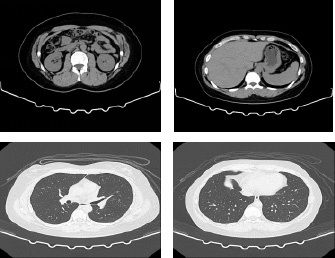

CT装置

- ・輪切りや色々な角度の3D 画像で人体の中を撮影出来ます。

- ・健診~精密検査まで幅広く使用します。

一般撮影の撮影画像

胸とお腹の輪切り画像

3D画像